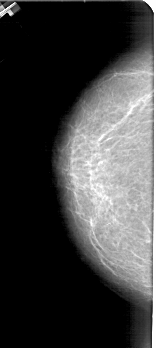

A_1433_1.RIGHT_MLO

LEFT_CC LINES 4861 PIXELS_PER_LINE 2176 BITS_PER_PIXEL 12 RESOLUTION 43.5 NON_OVERLAY